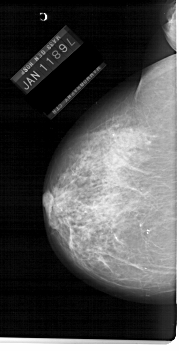

A_1230_1.LEFT_MLO

LEFT_MLO LINES 6871 PIXELS_PER_LINE 3721 BITS_PER_PIXEL 12 RESOLUTION 43.5 NON_OVERLAY